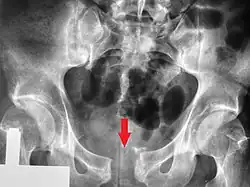

| A pelvic X-ray showing an open book fracture | |

Open book fracture

One specific kind of pelvic fracture is known as an 'open book' fracture. This is often the result of a heavy impact to the groin (pubis), a common motorcycling accident injury. In this kind of injury, the left and right halves of the pelvis are separated at front and rear, the front opening more than the rear, i.e. like an open book that falls to the ground and splits in the middle. Depending on the severity, this may require surgical reconstruction before rehabilitation.[12] Forces from an anterior or posterior direction, like head-on car accidents, usually cause external rotation of the hemipelvis, an “open-book” injury. Open fractures have an increased risk of infection and hemorrhaging from vessel injury, leading to higher mortality.[13]